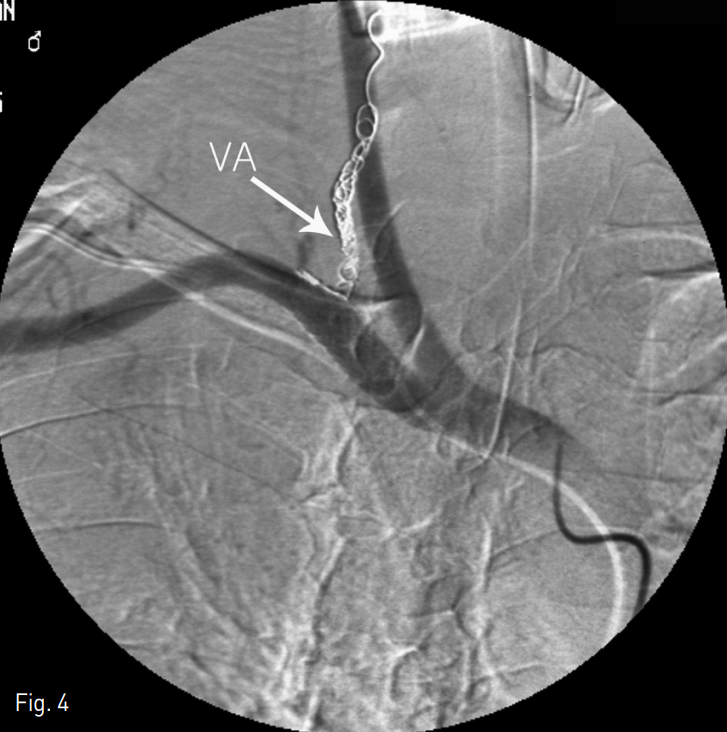

Fig. 4

Final selective right subclavian angiography revealing no filling of the pseudoaneurysm after coil embolization of proximal ver tebral artery (VA) and stent graft at subclavian artery across the VA origin.

추적검사에서 가성동맥류는 완전히 소실되었으며 환자는 합병증 없이 중환자실에서 잘 치료되었고 퇴원하였다.